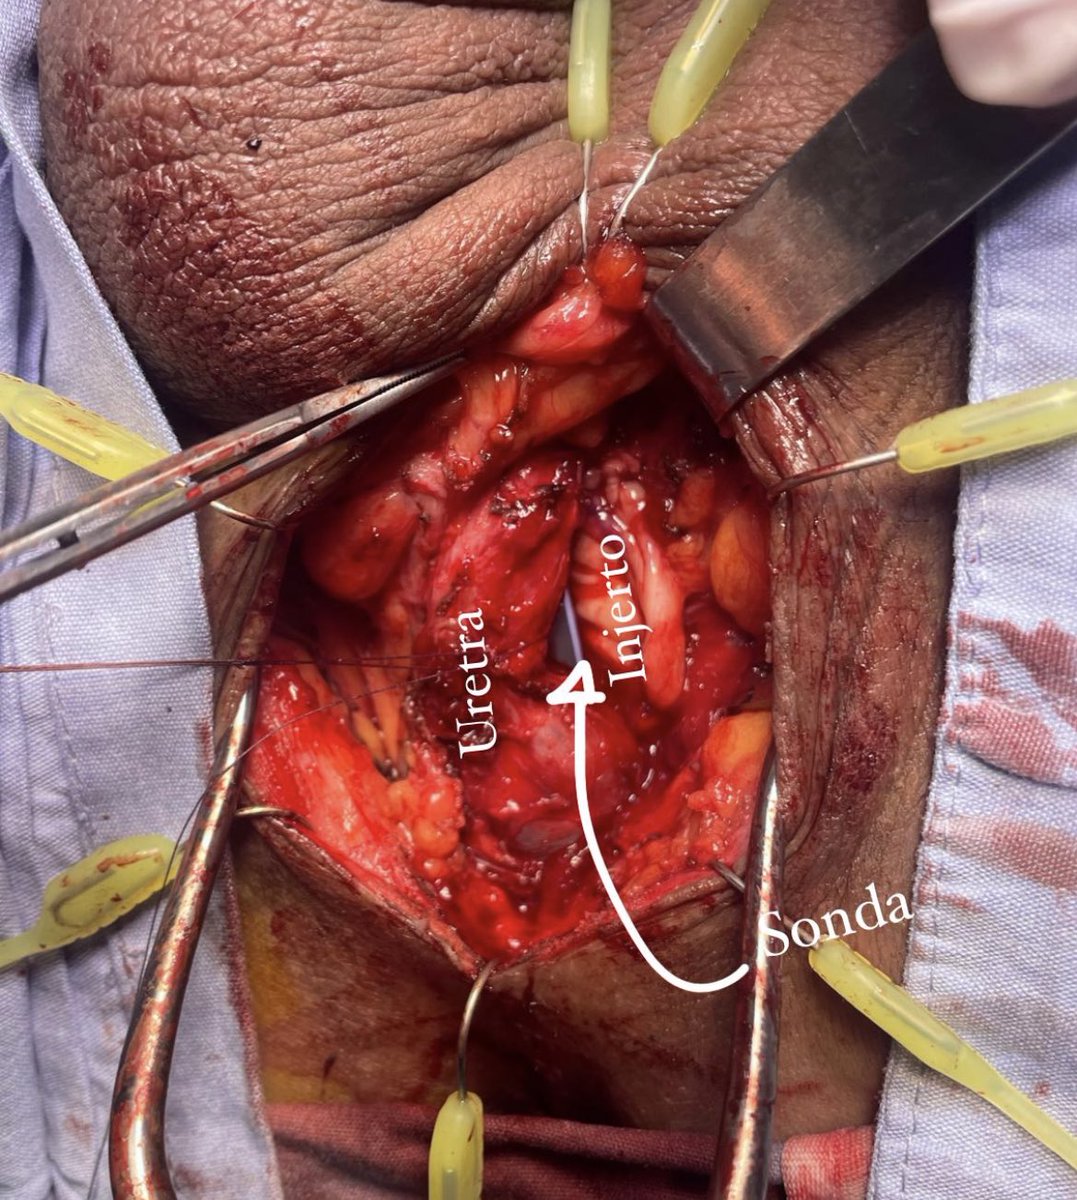

36a con estrechez uretral post instrumentación, con qmax 2.2 ml/s y 90% OR. Sin UTI previa, por la longitud decidí someterlo a plastia de uretra técnica Dr Sanjay Kulkarni con BMG. Con una disección de planos muy sencilla debido a no tener antecedente de tratamiento.

36a con estrechez uretral post instrumentación, con qmax 2.2 ml/s y 90% OR. Sin UTI previa, por la longitud decidí someterlo a plastia de uretra técnica <a href="/sanjaybkulkarni/">Dr Sanjay Kulkarni</a> con BMG. Con una disección de planos muy sencilla debido a no tener antecedente de tratamiento.